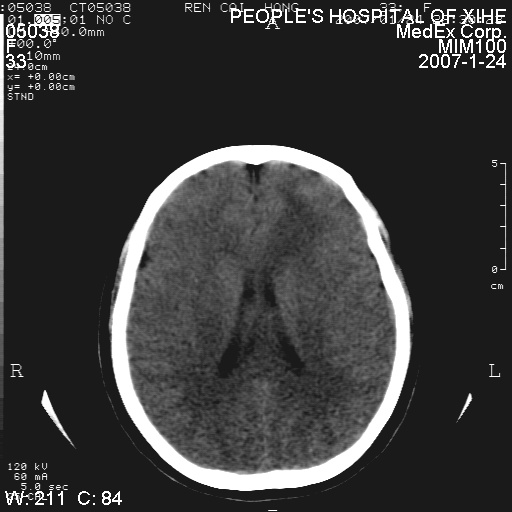

以下是引用卜一在2007-1-25 6:40:00的发言:[br]左侧额叶囊实混杂性病灶,多考虑胶质细胞瘤(ⅱ-ⅲ级),建议增强检查。[br]支持!

以下是引用wwwwtyy在2007-1-25 0:27:00的发言:[br]胶质瘤可能性大,不除外脑白质病变,建议强化

以下是引用xclzq_910在2007-1-25 12:41:00的发言:[br]左额叶条片状低密度灶,考虑占位,建议增强

以下是引用守望可可西里在2007-1-25 0:13:00的发言:[br]左侧额叶囊实混杂性病灶,多考虑胶质细胞瘤(ⅱ-ⅲ级),建议增强检查!